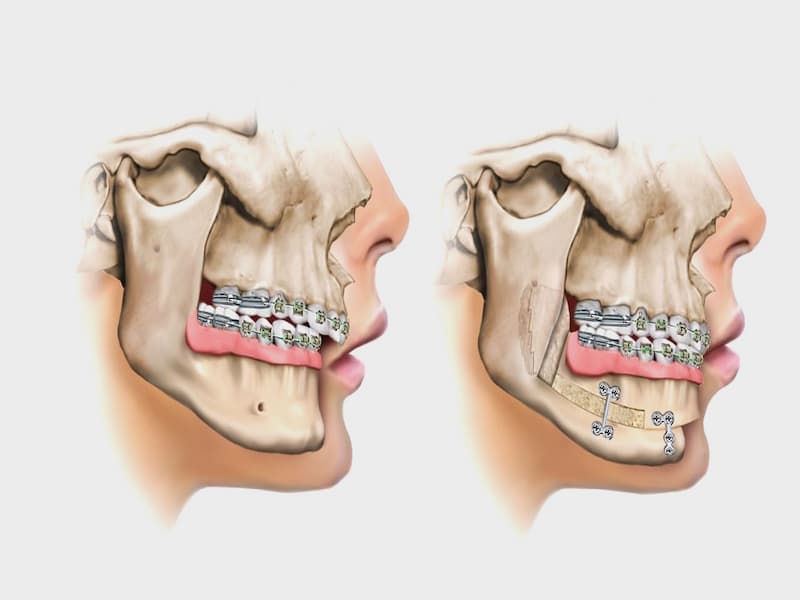

۱. استحکام: ایمپلنت جراح فکی با استفاده از یک فیکسچر وارد شده در آب مشترک فک در بیشتر موارد استحکام بالایی به دندان مصنوعی می دهد.

۲. زمان درمان: عمل جراحی ایمپلنت جراح فک ممکن است مدت زمان طولانی را در خود داشته باشد و نیاز به مراقبت های مکرر و صبوری دارد.

۳. عوارض: در برخی از موارد، عوارض مانند خونریزی، عفونت، و ترک خاصی در استخوان پایه ممکن است رخ دهند.